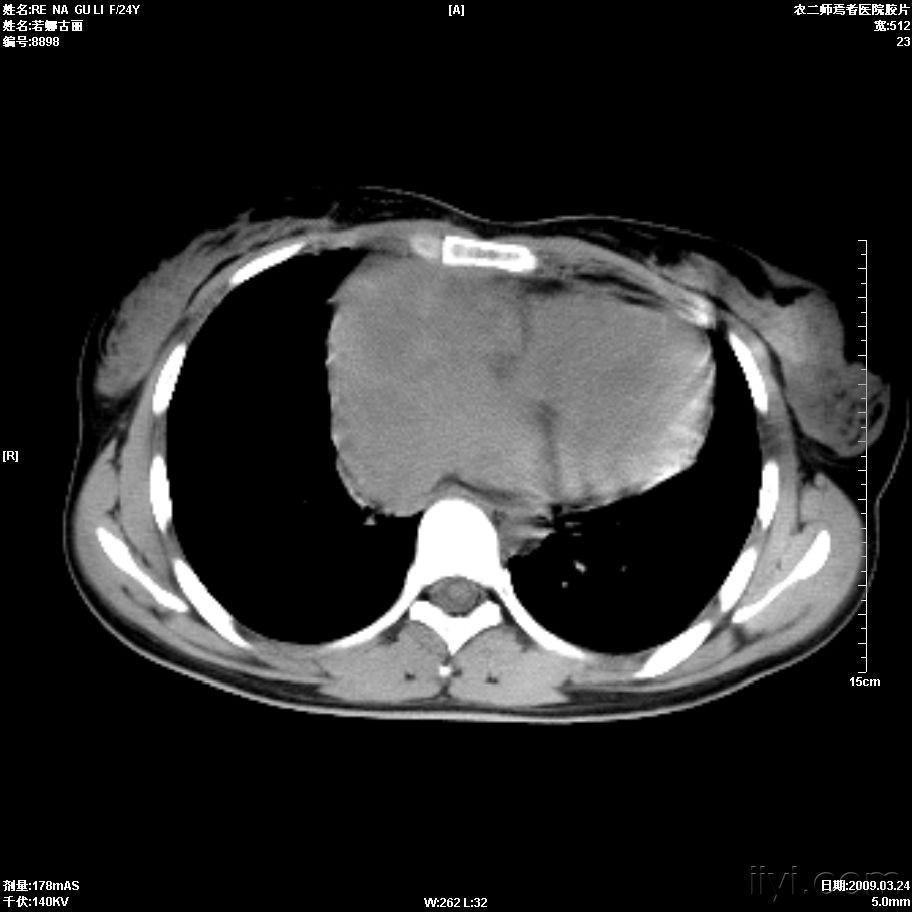

右心房壁肿块 - 医学影像学讨论版 - 爱爱医医学论坛

病例3:肺血基本正常,肺门影略大,双房影,心膈面延长.